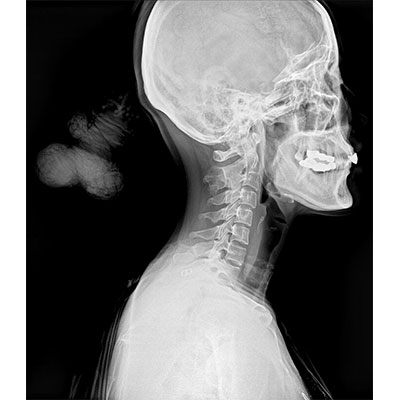

● 采用自主研發(fā)的技術(shù),在保證優(yōu)質(zhì)圖像的前提下,大大降低X射線劑量,用心呵護醫(yī)護工作者及患者的健康。

● 短曝光時間,便于老年人、兒童、殘疾人進行臨床拍攝。避免這類群體因不能有效控制身體運動等因素造成的運動偽影,提高攝片質(zhì)量及效率。